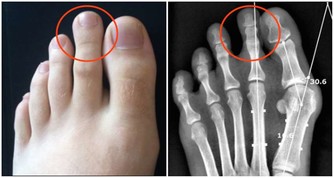

若脂肪主要分佈於臀部,這種梨型肥胖或皮下型肥胖,對中老年人的關節損傷也是一個大問題,不容忽視。因此,中老年人保持健康的體重,對身體健康來說至關重要。